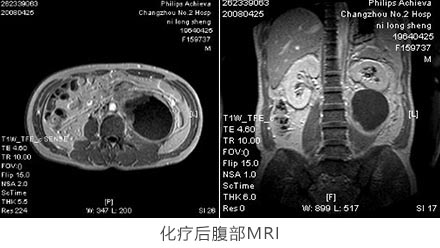

患者因晕厥检查发现腹膜后肿瘤,取活检穿刺标本,进行苏木精伊红染色,免疫组化分析波形蛋白和上皮膜抗原呈阳性,辅助腹部MRI检查。最后诊断为原发性后腹膜软组织肉瘤。患者肿瘤已侵犯大血管,无法切除,不宜进行手术治疗。 经肿块穿刺活检组织用ATP-肿瘤药敏实验检测后显示该肿瘤对顺铂(DDP)、阿霉素(ADM)和氮酰咪胺(DTIC)等敏感。确定治疗方案:DTIC 0.4 d1-3、DDP 30mg d1-4、ADM 30mg d1-3;同时辅以每日静脉补液体3000ml和5%碳酸氢钠125ml。2个化疗疗程后经腹部MRI检查,占位性病灶较前缩小,以囊性变坏死为主。